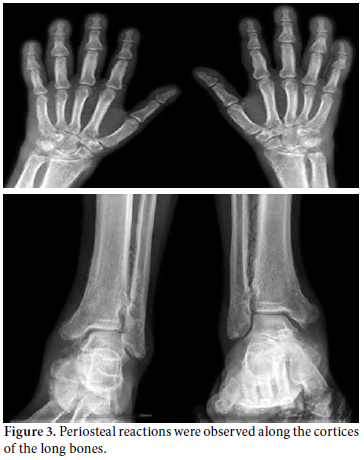

He had no other pertinent medical or familial history. His blood pressure was normal, and his outer appearance seemed to indicate acromegaly since the contour of the jaw was enlarged and long making his face appear coarse. The patient’s facial skin was oily with diffuse acne scars (Figure 1). He did not complain of hair loss, and cutis verticis gyrata was not present. His hands and feet were enlarged with thickened palms and heel pads. Clubbing of the fingers and toes was observed, and the skin of the lateral aspect of the proximal interphalangeal joints of the second to fifth finger was thickened (Figure 2). The patient’s palms were sweaty and moist, and both wrists and ankles were swollen and tender without the sense of warmth. Laboratory tests were normal for insulin-like growth factor-1 (IGF-1), thyroid function tests, and pepsinogen-1. His growth hormones were normally suppressed with glucose (75 g) loading. A peripheral blood test revealed a white blood count (WBC) of 8.300/μL, a hemoglobin count of 14.8 g/dL, and a platelet count of 368.000/μL. The erythrocyte sedimentation rate (ESR) and C-reactive protein (CRP) level were elevated at 56 mm/hr and CRP 1.8 mg/dL, respectively. Negative results were obtained for rheumatoid factor, anti-cyclic citrullinated protein (anti-CCP) antibodies, and HLA-B27. The antinuclear antibody test (ANA) was weakly positive (1:40, nucleolar), but the extractable nuclear antigen (ENA) results were negative for anti-dsDNA, RNP, Ro/La, Smith, Scl70, centromere, and Jo-1 antibodies. X-rays revealed periosteal thickening of the long bones, from the epiphyses to the metaphyses but sparing the diaphyses (Figure 3). The vertebral spines, proximal ends of the humeruses and femurs, and lateral Sellar’s view of the skull showed normal bony contours. On bone scintigraphy, a diffusely increased uptake of isotope was observed along the cortical lining of the long bones, but there was no abnormal uptake of the isotope suggesting joint pathology. For the evaluation of intermittent epigastric soreness, which had lasted for years, a gastrofibroscopy was done, and the results were nonspecific. The presence of clubbing and radiographic evidence of periostosis of the tubular bones without underlying diseases correctly diagnosed PDP in this patient. He was prescribed non-steroidal anti-inflammatory drugs (NSAIDs) on an as needed basis, and a single dose of intravenous ibandronate sodium (3 mg). The pain subsided, and the patient continues to be followed up.